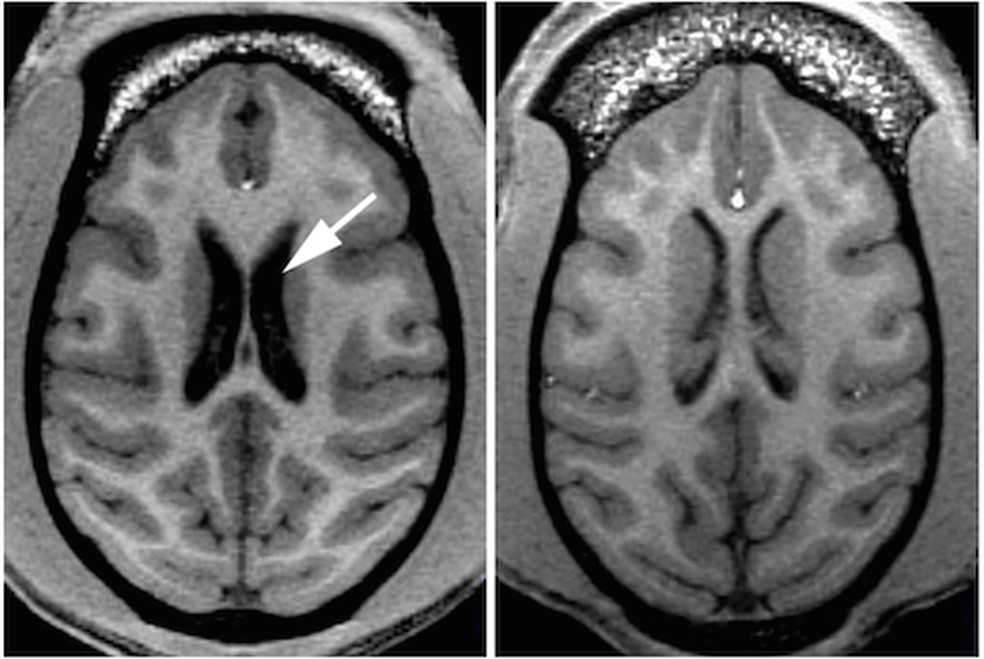

Cérebros de macacos geneticamente modificados mostram a perda de massa cerebral e a atrofia cerebral gradual (à esquerda) de um indivíduo com a doença de Huntington — Foto: Emory University/PLOS One A doença de Huntington afeta cerca de 7 a cada 100 mil pessoas, e é causada por uma mutação genética sem cura. O HTT, único gene responsável pela doença, foi descoberto em 1993 e tem caráter dominante, ou seja, basta uma cópia do gene defeituoso para tê-la. Assim, filhos de pais afetados têm 50% de chance de herdar a mutação que causa problemas cognitivos, motores e psíquicos.